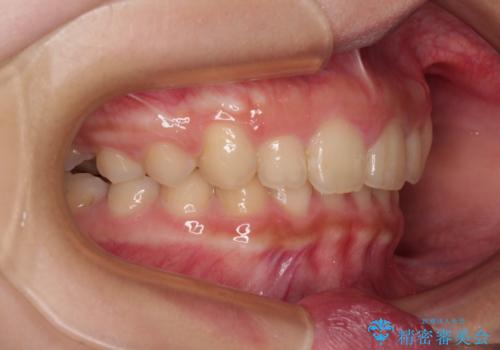

飛び出した前歯をインビザラインですっきりと

- 深い咬み合わせと上顎前歯の突出感を気にして来院された患者様です。

当院では通常、臼歯の咬合が理想的な位置に対して上顎が前方位にある場合。ワイヤー矯正または補助装置の併用したインビザライン矯正を選択しています。

今回は、できるところまででいいのでインビザライン単体で治療をしたいという希望があったため、インビザラインにて矯正治療を行うこととしました。

正面や横からの写真ではきれいに治っており、患者様は大変満足のいく仕上がりとなりましたが、深い咬み合わせの改善は不十分で、奥歯の咬み合わせも改善させることができませんでした。

インビザラインは、咬合力の強い方ですと、奥歯が歯肉内にめり込んでしまうため、前歯が強く接触してしまうことがあります。

こちらの方は、奥歯はしっかりと噛んだのですが、歯肉にめり込んでしまったことで、歯肉が腫れやすくなってしまいました。